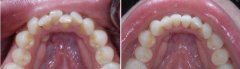

矫正牙齿拥挤需要多少钱?

牙齿拥挤非常影响面部美观,还会使患者出现咀嚼不便等问题,矫正牙齿拥挤非...【详细】

牙齿拥挤为什么会出现?

牙齿拥挤在人群中很常见,不但会影响到患者外观,严重的会使患者牙齿外露,...【详细】